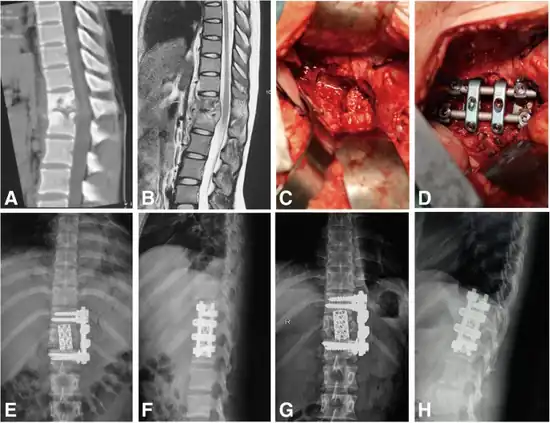

Surgery

a) Preoperative CT b) Preoperative MRI c,d) intraoperative debridement, titanium cage strut fusion e,f) postoperative radiographs g,h) radiograph follow-up[25]

Surgical intervention is required for patients with Pott's disease in the event that there is a need for tissue sampling to clarify diagnoses, resistance to chemotherapy, neurologic deficits , paravertebral abscesses formed from bacterial induced immune response, and kyphotic deformities leading to instability of the spine.[1] However, surgery is up to shared clinical decision making and not an intervention that is defaulted to, as guidelines tend to lead towards less invasive procedures such as chemotherapy and anti-tuberculosis medications.[26]

Typical surgical techniques used are as follows:

• Posterior decompression and fusion with bone autografts[1][27]

• Anterior debridement/decompression and fusion with bone autografts[1][27]

• Anterior debridement/decompression and fusion followed by simultaneous or sequential posterior fusion with instrumentation[1][27]

• Posterior fusion with instrumentation followed by simultaneous or sequential anterior debridement/decompression and fusion[1][27]